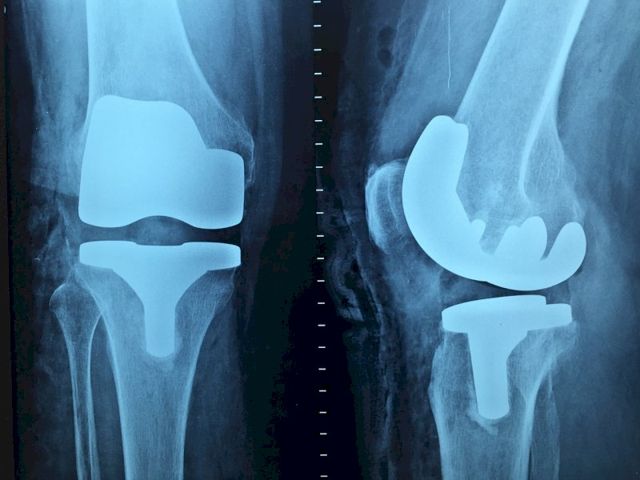

«Плохо группируются»: в Екатеринбурге растет количество «уличных» переломов17 февраля 2021 в 10:35